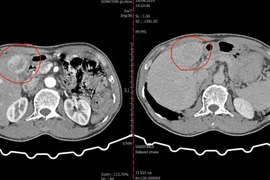

Nút mạch hóa chất cứu người bệnh bị ung thư gan nặng

Với một người bệnh lớn tuổi, suy kiệt, lại mắc bệnh hô hấp nặng nề, việc phẫu thuật cắt gan sẽ rất rủi ro trong và sau mổ.